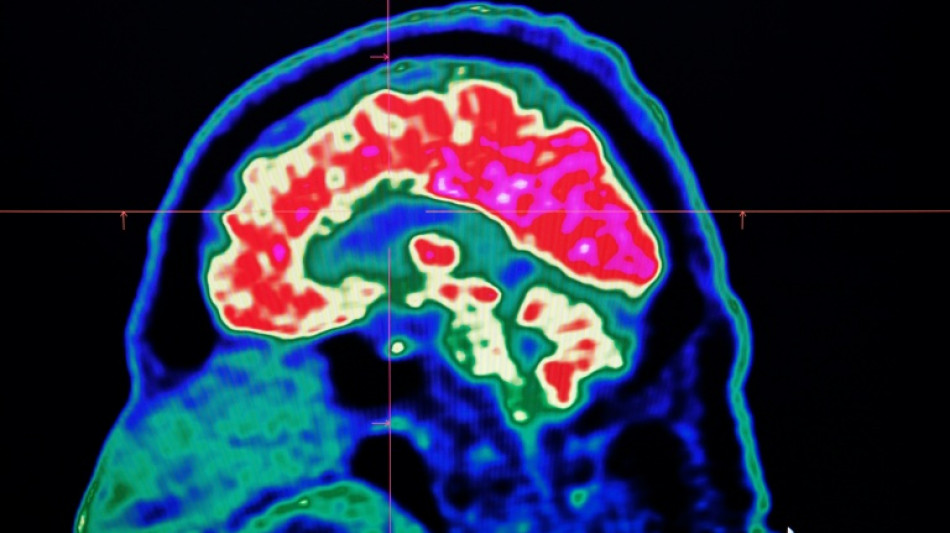

In 2021, health officials in New Brunswick launched an investigation involving 48 patients with a range of neurological symptoms but no apparent common illness. These included muscle spasms, memory loss, hallucinations and balance issues.

Some in the province of less than a million people began describing the condition as a mystery brain disease.

Marrero said that while the condition could not be diagnosed, he believed the patients had elevated levels of certain substances -- like herbicides or toxic metals -- in their systems, suggesting an environmental cause for the illness.